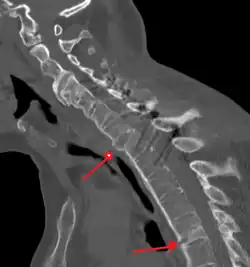

X-rays

The earliest changes demonstrable by plain X-ray shows erosions and sclerosis in sacroiliac joints. Progression of the erosions leads to widening of the joint space and bony sclerosis. X-ray spine can reveal squaring of vertebrae with bony spur formation called syndesmophyte. This causes the bamboo spine appearance. A drawback of X-ray diagnosis is the signs and symptoms of AS have usually been established as long as 7–10 years prior to X-ray-evident changes occurring on a plain film X-ray, which means a delay of as long as 10 years before adequate therapies can be introduced.[25]

Options for earlier diagnosis are tomography and MRI of the sacroiliac joints, but the reliability of these tests is still unclear.

-

Lateral X-ray of the mid back in ankylosing spondylitis -

Lateral X-ray of the neck in ankylosing spondylitis -

X-ray showing bamboo spine in a person with ankylosing spondylitis -

CT scan showing bamboo spine in ankylosing spondylitis -